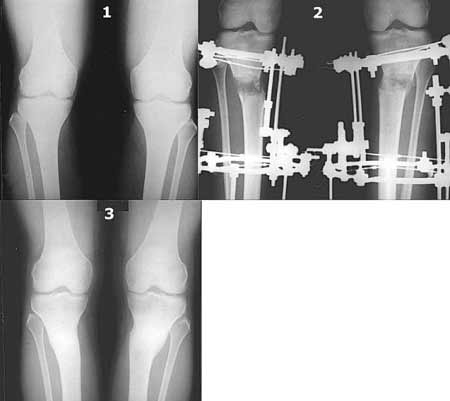

Картинки - в приложении.Будут вопросы - готов ответить.

Ещё картинка - схема. Хотя у Соломина всё написано.

Вот ещё картинки, которые отправлял в Ортопод. Коррекция кривизны и удлинение на 3 см.

Мне представляется оптимальным на уровне 3-4 линии (т.е. как раз посредине отмеченной зоны). Если рассчимтываешь делать медиализацию, то параллельно суставной поверхности, иначе просто не сдвинешь без джистракции - отломки зацепятся. Если без медиализации - то вообще не имеет значения.

a>> Это значительно улучшает эстетический эффект, придавая полноту ногам.

a>> Мне лично нравится:)

AC> В данном случае это насколько желательно?

Если опыт единичный, то не усложняй. И так будет хорошо.

И зачем латерализация периферического фрагмента. Я всегда делаю медиализацию. См схему. И для данного случая медиализация подходит как нельзя лучше.